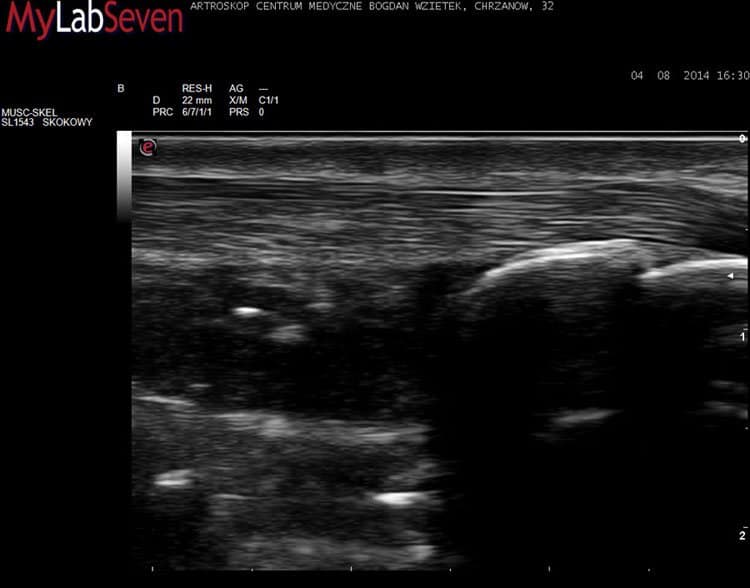

Przykładowe obrazy USG